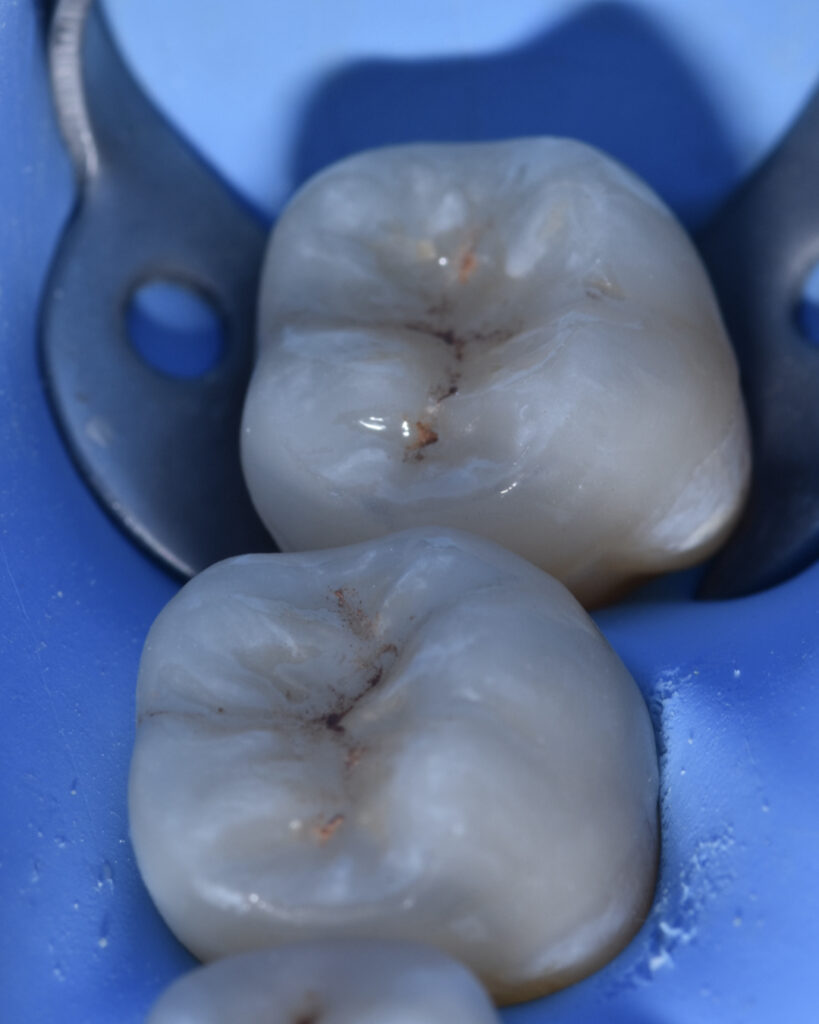

Tooth 3.7 presented a large MOD carious lesion, with both distal cusps and the mesiolingual cusp structurally compromised.